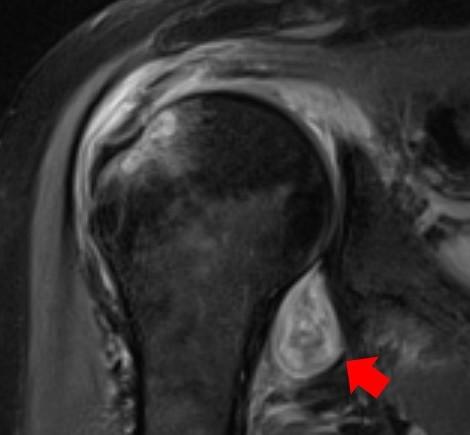

image: MRI image of a patient's shoulder. The red arrow points to inflammation in the joint. The COVID virus triggered rheumatoid arthritis in this patient with prolonged shoulder pain after other covid symptoms resolved.

For example, Deshmukh said, if a patient has persistent shoulder pain that started after contracting COVID, their primary care provider might order an MRI/ultrasound. If a radiologist knows COVID can trigger inflammatory arthritis and imaging shows joint inflammation, then they can send a patient to a rheumatologist for evaluation.